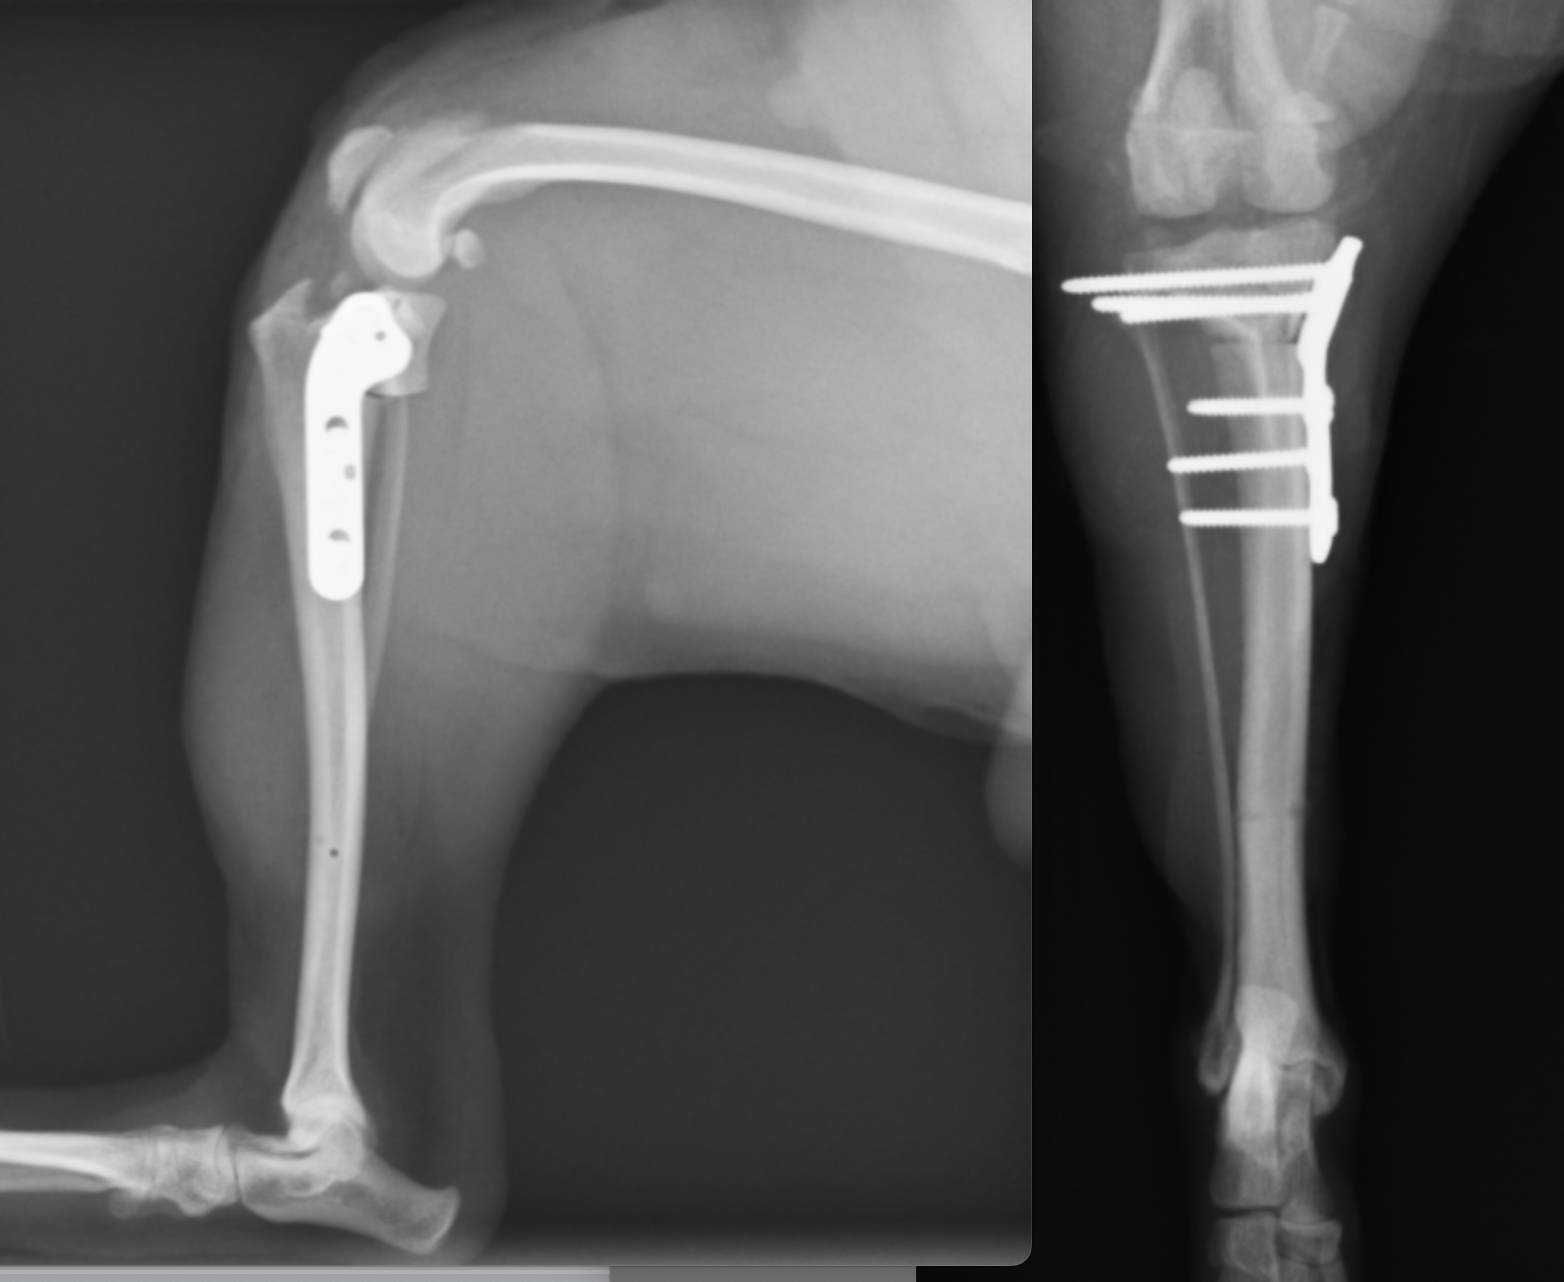

術後のレントゲン画像です。先程までずれていた矢印が合っているのがわかります。

またTPAと呼ばれる角度も小さくなっているのが確認できます(6°)。6°前後が理想的と言われています。

35kgの黒ラブラドールです。術後TPAは7°と、理想的な角度となっています。この症例もすぐに歩きだし、跛行もなくなりました。

40kgのバーニーズマウンテンドッグです。11歳と高齢でしたが、7日目には跛行があったものの、4本足で帰宅することが可能でした。